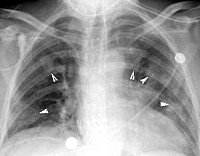

Проводятся кожные аллергологические тесты с экстрактом из аспергилл (выявляется типичная реакция немедленного типа). Диагноз аллергического бронхолегочного аспергиллеза подтверждается при определении повышенного уровня общего иммуноглобулина E и специфических IgE и IgG к Aspergillus fumigatus в сыворотке крови. При проведении бронхографии и компьютерной томографии выявляются проксимальные бронхоэктазы, «летучие» инфильтраты в легких.